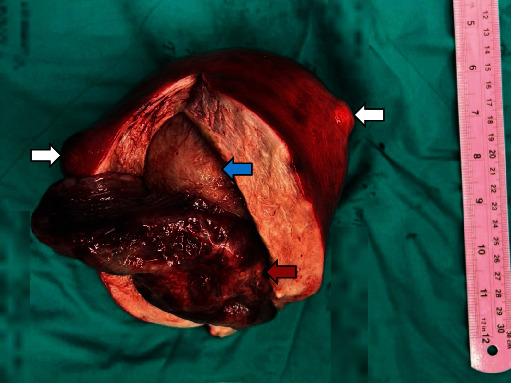

子宫内膜息肉是子宫内膜腺体和基质在子宫腔内无序生长的良性肿瘤。它们与不孕症、异常子宫出血和使用他莫昔芬有关。虽然大多数息肉的大小小于 2 厘米,但罕见的巨大息肉会引起恶性肿瘤的担忧。我们报告了一例 58 岁女性的 15 厘米巨大子宫内膜息肉病例,该女性有服用他莫昔芬的病史,并以便秘为常见主诉。此外,我们还对巨型子宫内膜息肉病例进行了文献综述。该病例是迄今为止报告的最大的子宫内膜息肉。

Endometrial polyps are benign disorganized growth of endometrial glands and stroma in the uterine cavity. They are associated with subfertility, abnormal uterine bleeding, and tamoxifen use. While most polyps are smaller than 2 cm in size, rare giant polyps can cause concerns over malignancy. We report a case of a 15 cm giant endometrial polyp in a 58-year-old woman with a history of tamoxifen use who presented with an uncommon complaint of constipation. Additionally, a literature review of giant endometrial polyp cases is presented. This case represents the largest reported endometrial polyp to date.